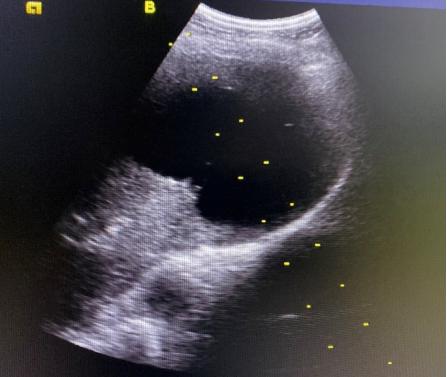

B超引导下肝囊肿穿刺抽液及硬化剂治疗